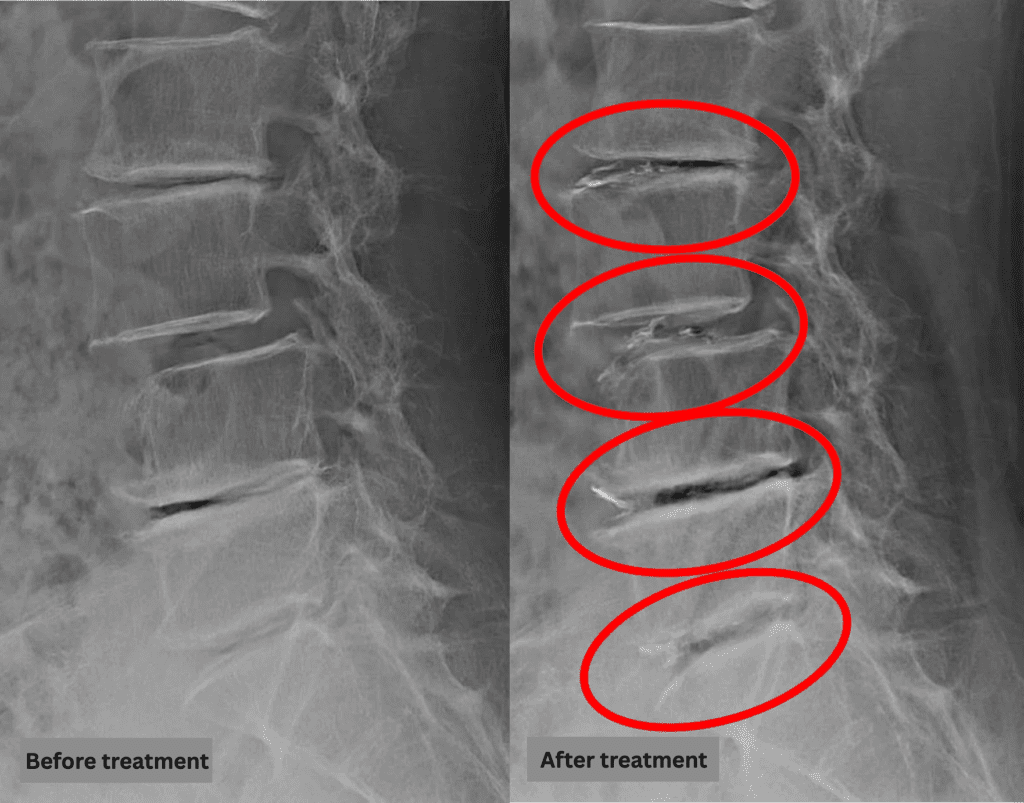

After consulting with the patient, the Cellgel Method was performed on L2/3, 3/4, 4/5 and 5/s.

The treatment was performed by Dr. Ohara.

The treatment took about 55 minutes.

After resting in the recovery room, the patient was able to walk home unaided.